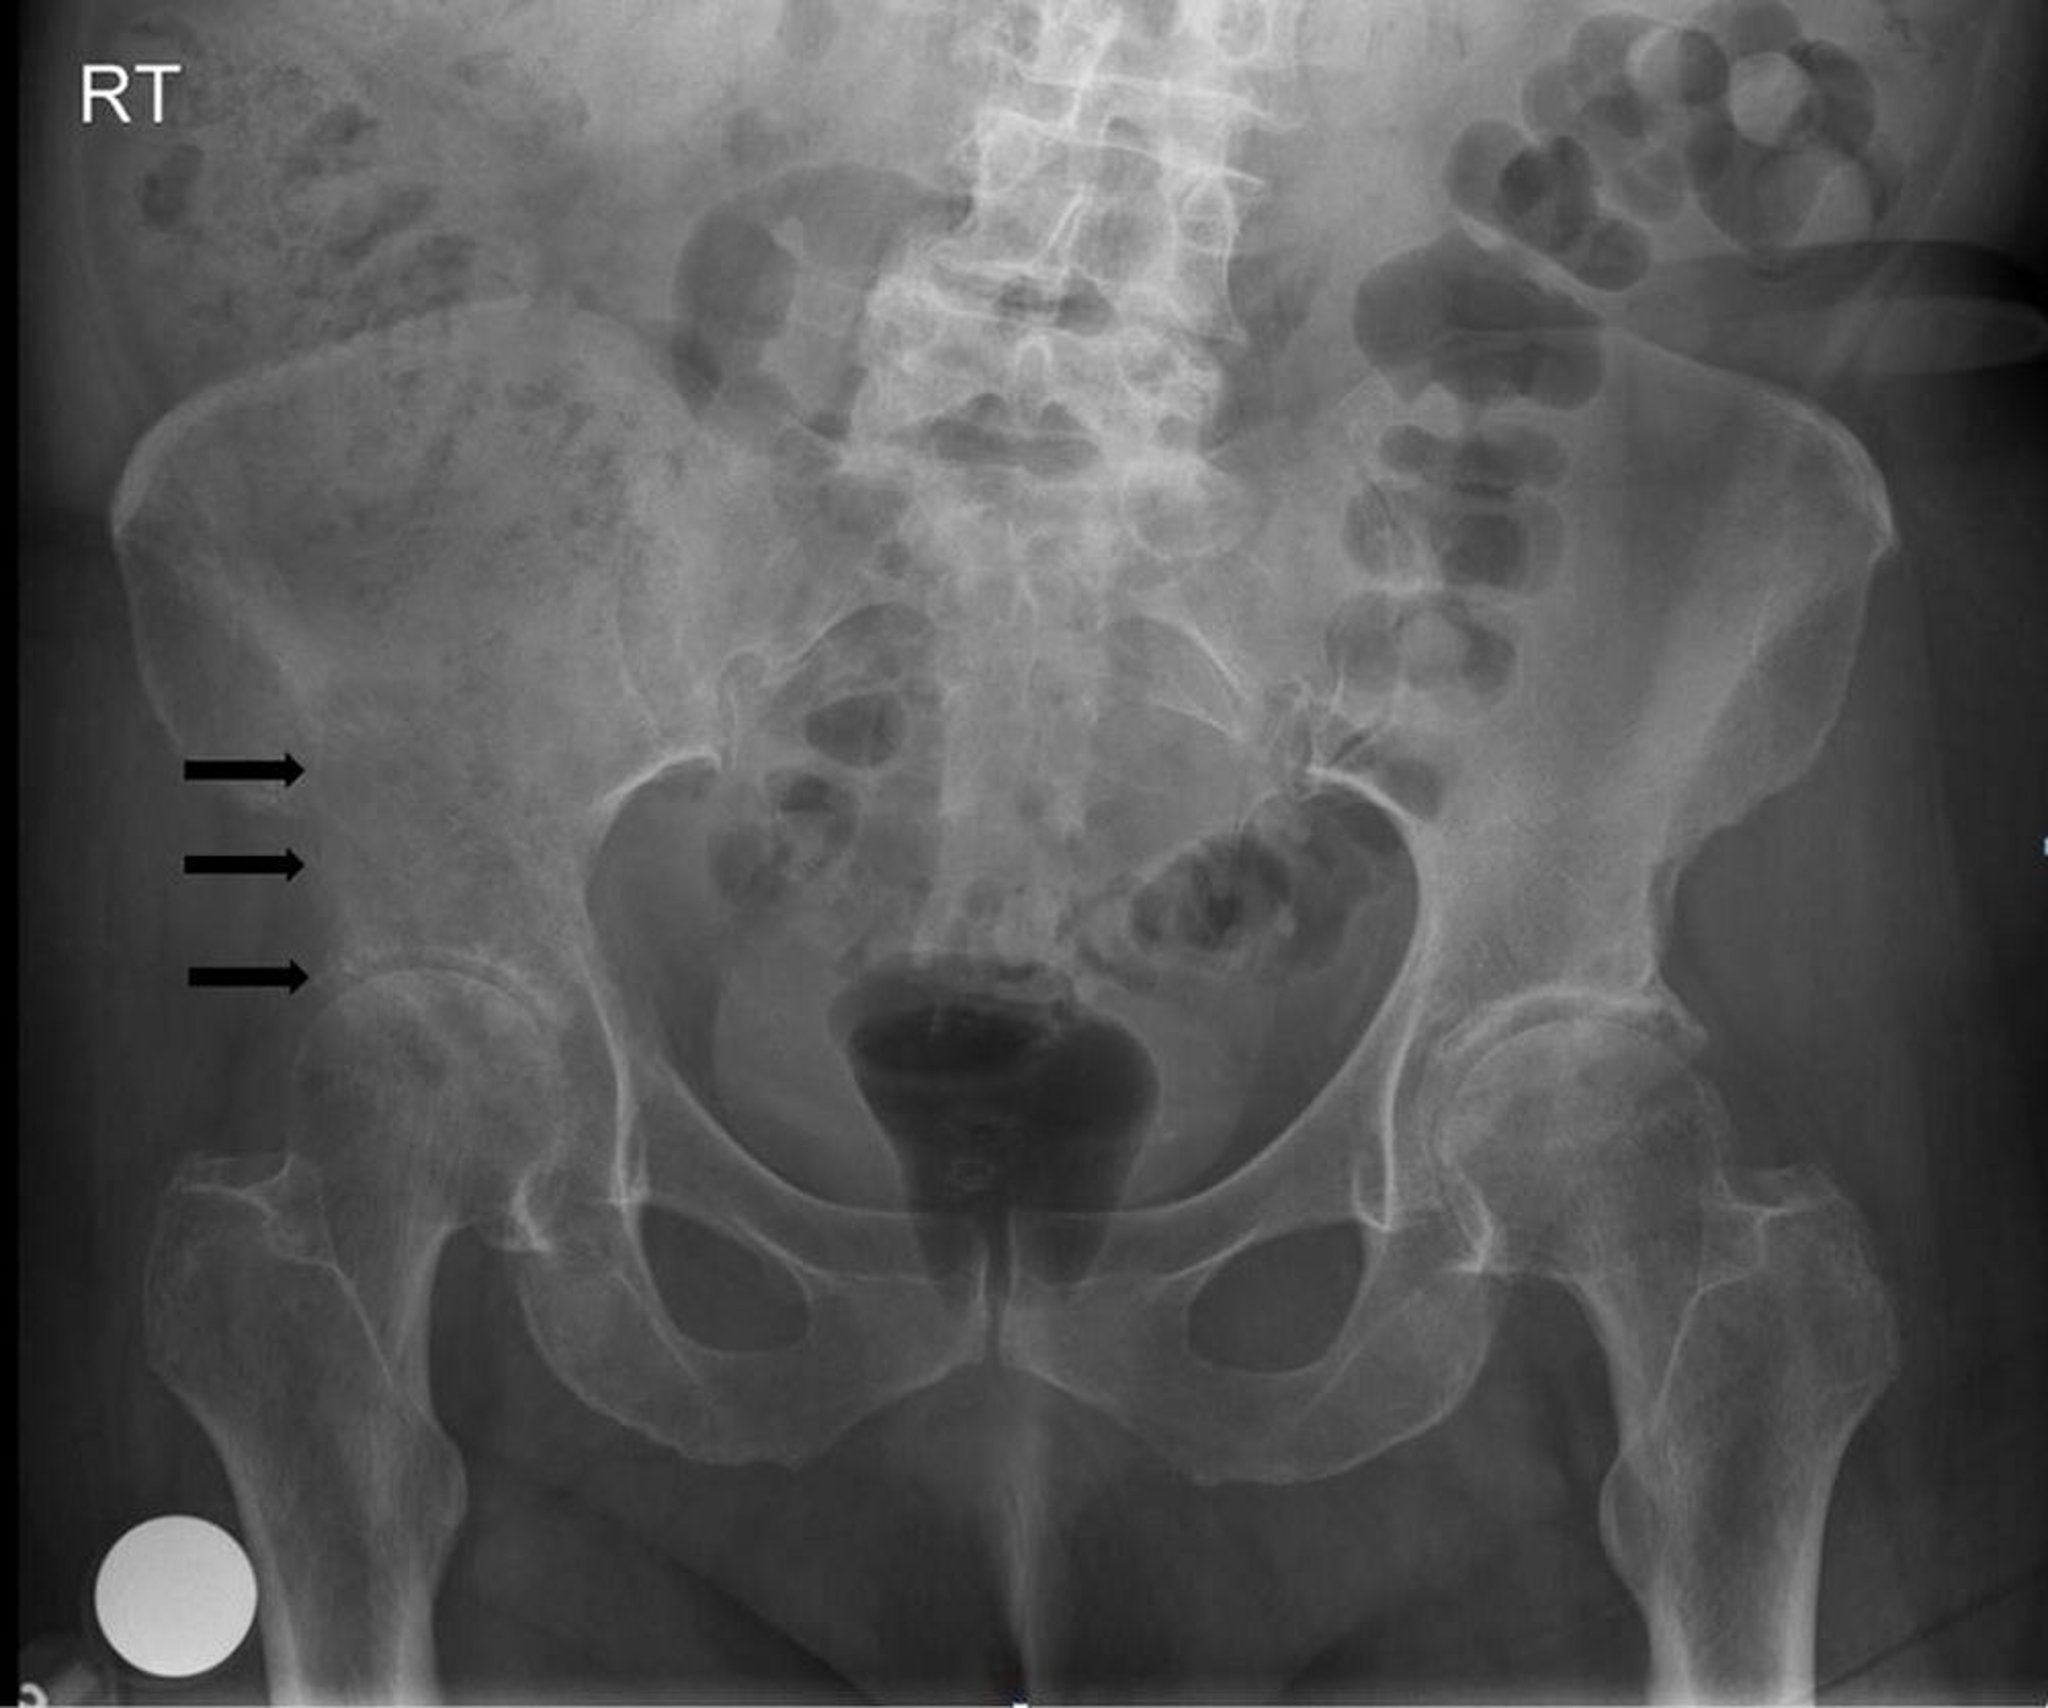

Cancer osseux métastatique

Cette radiographie du bassin montre une lésion lytique, destructrice au niveau et au-dessus de l'acétabulum droit (flèches), compatible avec une métastase.

Image courtoisie de Michael J. Joyce, MD, and Hakan Ilaslan, MD.